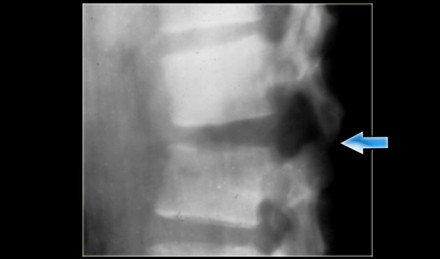

On the left another example of a Chance fracture.

Chance fracture (3)

On the left a Chance variant.

This is a pure ligamentous injury, which is analogous to bilateral

interfacet dislocation, which is also a pure ligamentous injury.

There is rupture of the interspinous ligament, dislocation of the facet joints and a horizontal rupture of the disc.

Pure ligamentous and combined osseous / ligamentous variants have an increased risk of instability compared to the osseus type.

Always look for a split of the posterior elements, disc widening or widening of the spinous processes and facets.